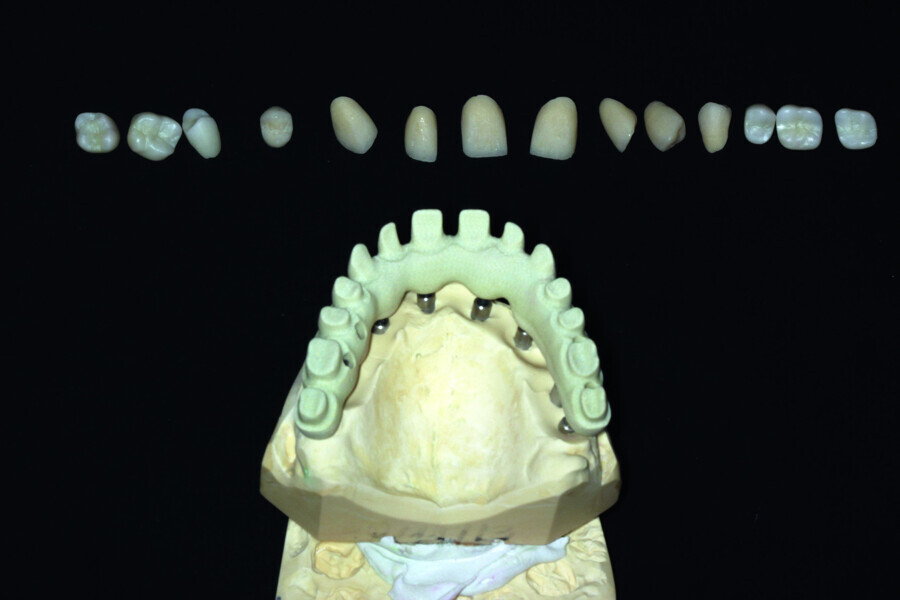

Fig. 13: Porcelain crowns prepared for testing.

Fig. 14: Porcelain crowns based on a model prior to veneering by means of a pink composite.